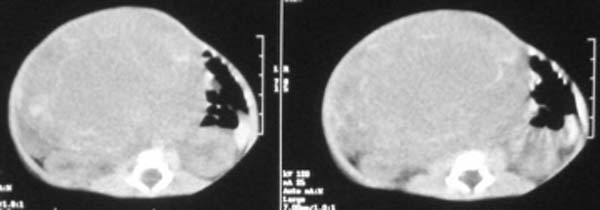

这个女孩刚出生一天,肚子比较大,没任何症状.比较少见,请大家积极发言!!

这个病例定位诊断:1、可以肯定肿块不在肝脏。2、肿块在腹膜后,因为肠管向前侧方推移,肾脏明显向后推挤,腹主动脉及下腔静脉被肿块包绕。

定性诊断比较困难,该病例肿块为实质性,小儿最常见的腹膜后肿瘤第一位应该是-----神经母细胞瘤!

我的意见是-----定位诊断是“1、可以肯定肿块不在肝脏。2、肿块在腹膜后,因为肠管向前侧方推移,肾脏明显向后推挤,腹主动脉及下腔静脉被肿块包绕。”